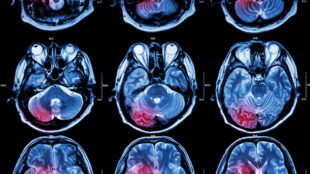

Gener gör olika när det gäller hjärntumörer

Två gener spelar viktiga roller för hur elakartad cancer bildas i hjärnan. En gen håller tillbaka bildandet av tumören,...

Blodflödet i hjärnan kan visa på bäst behandling

Stört blodflöde förekommer vid många sjukdomar. Nu kan blodflödet i hjärnan analyseras automatiskt med ny kraftfull...